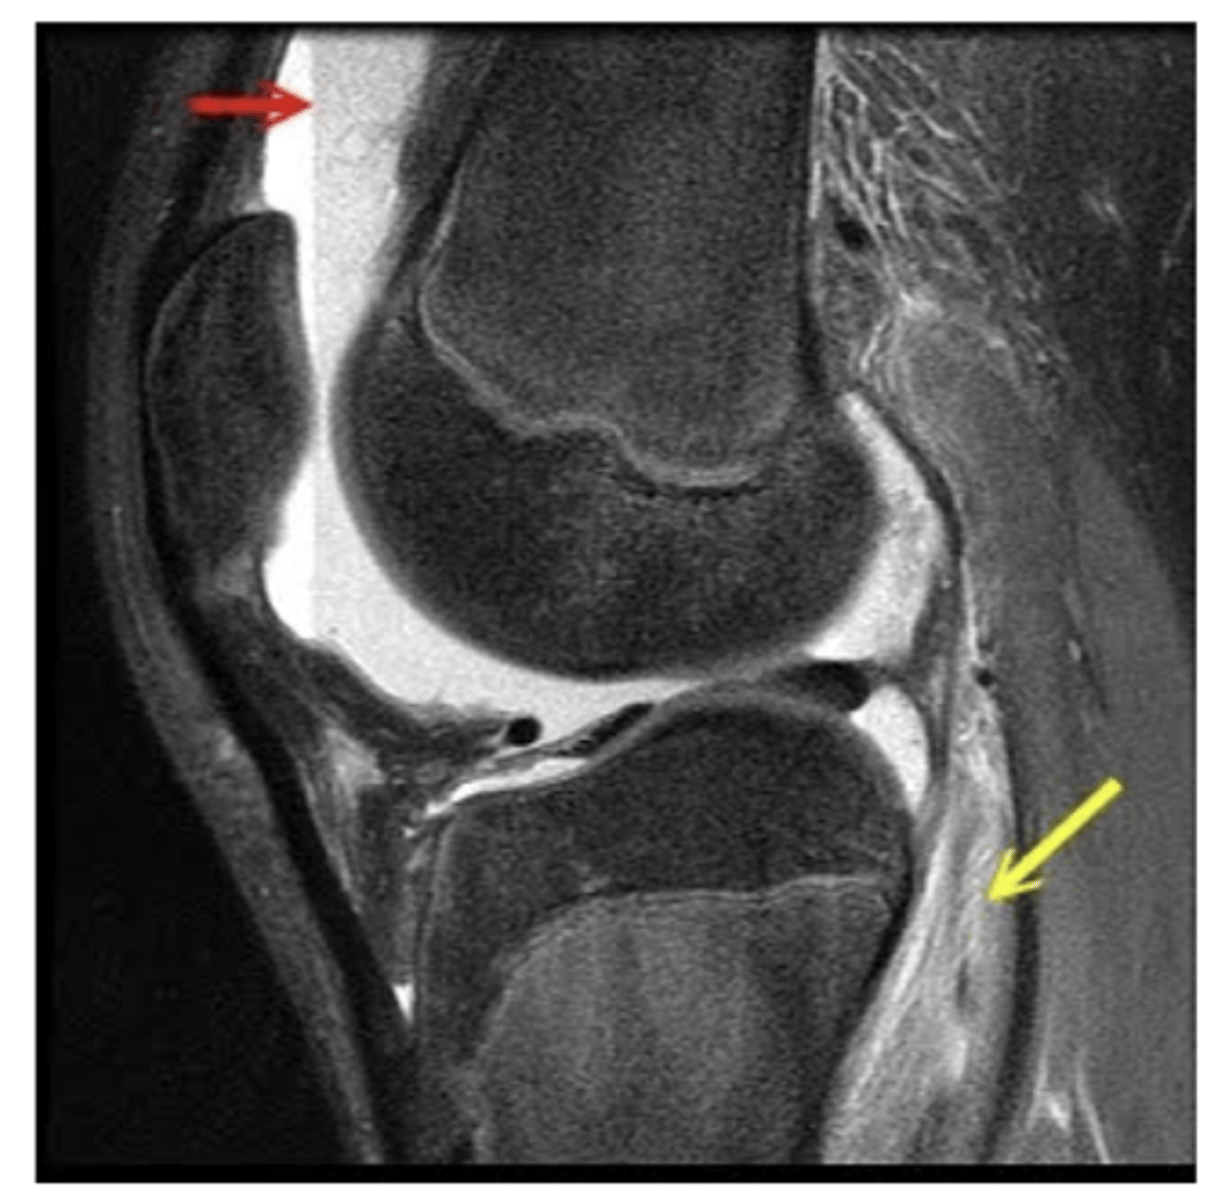

PCL (runs from posterior & inferior --> to anterior & superior)

Which structure is the white arrow pointing too?

Tear of the PCL -- normally, ligaments are pulled taut and appear straight; if they are torn, they appear wavy and/or curved over

Define the pathology. How do you know?